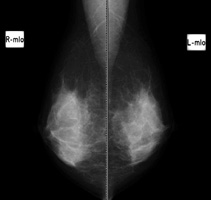

マンモグラフィ検査

マンモグラフィ装置

マンモグラフィとは乳房のX線撮影のことです。乳癌の初期症状である小さな石灰化を写し出せるのが大きな特徴です。触診では触れない小さな乳がんを写し出すことが出来ます。

検査は上半身の衣類を脱いでから、専用の検査着に着替えて行います。乳腺組織を見やすくするために、乳房を圧迫板で片方ずつ挟んで撮影します。標準撮影は、左右の乳房を上下方向と斜め横方向の4回で検査時間は 10 分程度です。

圧迫伸展して撮影することで乳腺組織や病変の重なりが減り、正しい診断を行いやすくします。痛みをともなう場合もありますが、X線被曝量を減らす効果もあります。痛みが強いときは加減しますので、遠慮なくおっしゃってください。生理が終わってから1週間くらいの間は、乳腺が柔らかいので、痛みが減る傾向があります。

乳房トモシンセシスについて

トモシンセシス撮影とは、マンモグラフィの 3D 画像のことです。従来のマンモグラフィと同様に、乳房を挟んだ状態で複数の方向から撮影を行い、1mmスライスの細かい画像を作成します。通常のマンモグラフィに追加して撮影することで、乳腺の重なりによって発見しづらかった病変が見つけやすくなります。厚みのある乳房内の重なりを減らすことにより、乳腺の奥の病変の観察がしやすくなります。一回の圧迫時間は 10〜15 秒程度で、ぶれないように息を止めて撮影します。

2D撮影

トモシンセシス撮影